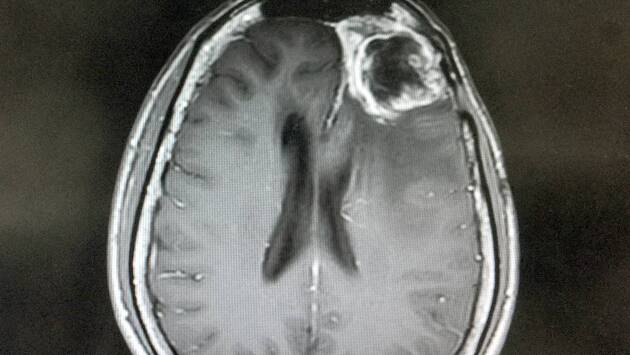

Глиобластома, один из самых агрессивных видов рака мозга, использует глюкозу иначе, чем здоровые клетки. Исследование, опубликованное в Nature, показало: вместо получения энергии и синтеза нейромедиаторов опухоль перенастраивает сахарный обмен, превращая глюкозу в строительные блоки ДНК и РНК. Это ускоряет деление и распространение раковых клеток.

Ученые проследили метаболизм с помощью меченой глюкозы у пациентов и мышей с опухолями. В коре мозга углерод из сахара использовался для цикла Кребса и работы нейротрансмиттеров, тогда как опухоль отключала эти процессы и добирала недостающие ресурсы из аминокислот, особенно серина.

Когда мышей переводили на диету с ограничением серина и глицина, глиобластома теряла часть топлива для синтеза нуклеотидов. В результате ее рост замедлялся, а стандартные химио- и радиотерапия становилась более эффективными.